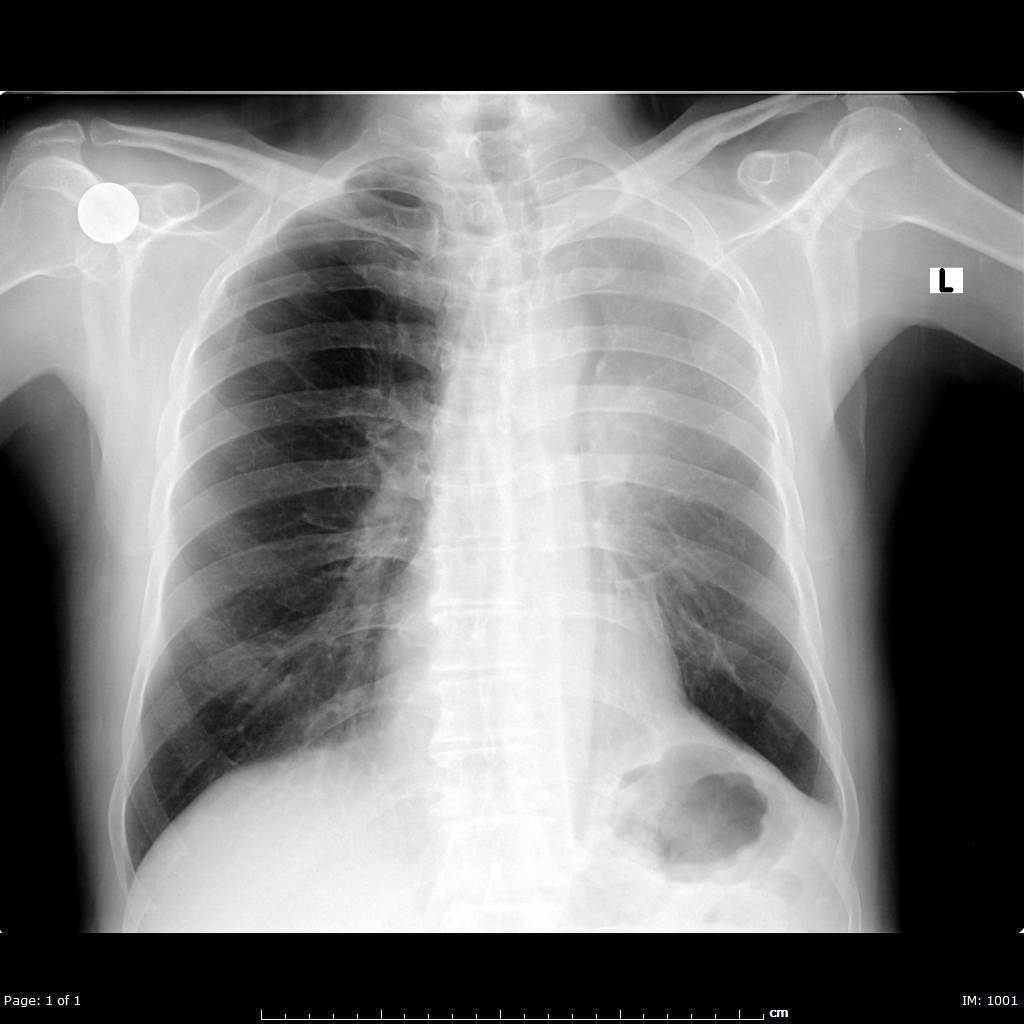

Lung Azygous fissue

Accessory fissure present in less than 1% of patients, seen in the presence of an azygous lobe. An azygous lobe is an anatomic varian where the right upper lobe apical or posterior segments are encased in their own parietal and visceral pleura.